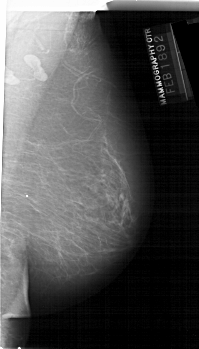

A_1132_1.RIGHT_MLO

RIGHT_MLO LINES 6616 PIXELS_PER_LINE 3766 BITS_PER_PIXEL 12 RESOLUTION 43.5 NON_OVERLAY